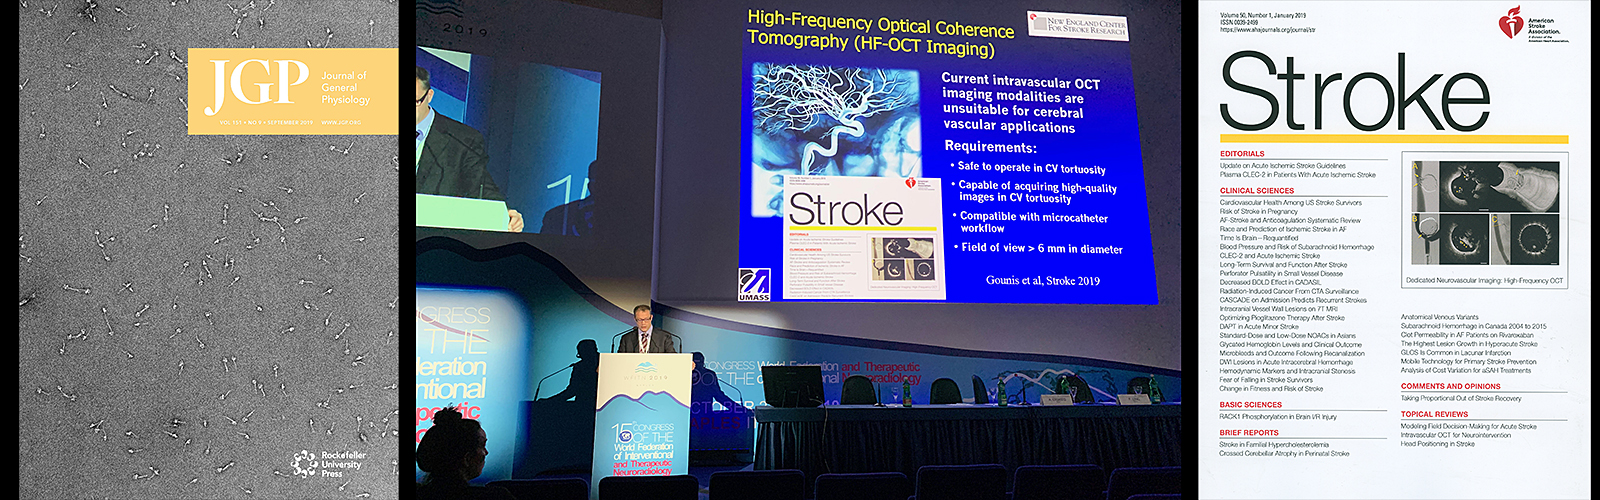

Radiology Research

Our mission is simple: to bring scientific advances in medical imaging to clinical application. Our current major areas of focus include Interventional Neuroradiology, Biomarker Development, Molecular Imaging, Nuclear Medicine Physics, and Cell Biology. Learn more.